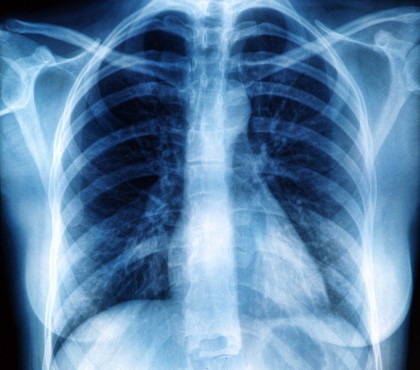

Chirurgia de reducere a volumului pulmonar pentru emfizem: rezultate mai bune decât se credea inițial

Un nou studiu prezentat la Întâlnirea Anuală a Societății Chirurgilor Toracici din 2025 sugerează că pacienții cu emfizem avansat care sunt supuși chirurgiei de reducere a volumului pulmonar (LVRS) au rezultate mai bune decât s-a raportat anterior. Mai mult, aceștia ar putea avea o supraviețuire mai lungă și mai puține complicații decât cei care aleg plasarea de valve endobronșice (EBV), o alternativă minim invazivă introdusă în tratamentul bronho-pneumopatiei obstructive cronice (BPOC) și al emfizemului sever.

Rezultatele sugerează că LVRS ar trebui reconsiderată ca opțiune terapeutică principală în tratamentul emfizemului sever, având în vedere îmbunătățirile semnificative ale tehnicilor chirurgicale. Deși EBV rămâne o soluție mai puțin invazivă, datele actuale indică un beneficiu superior pentru pacienții care aleg intervenția chirurgicală.

Dr. Hayanga subliniază că pacienții par să aibă rezultate mult mai bune după chirurgie decât în trecut, ceea ce ar trebui să determine o revizuire a strategiilor de tratament pentru această afecțiune gravă.